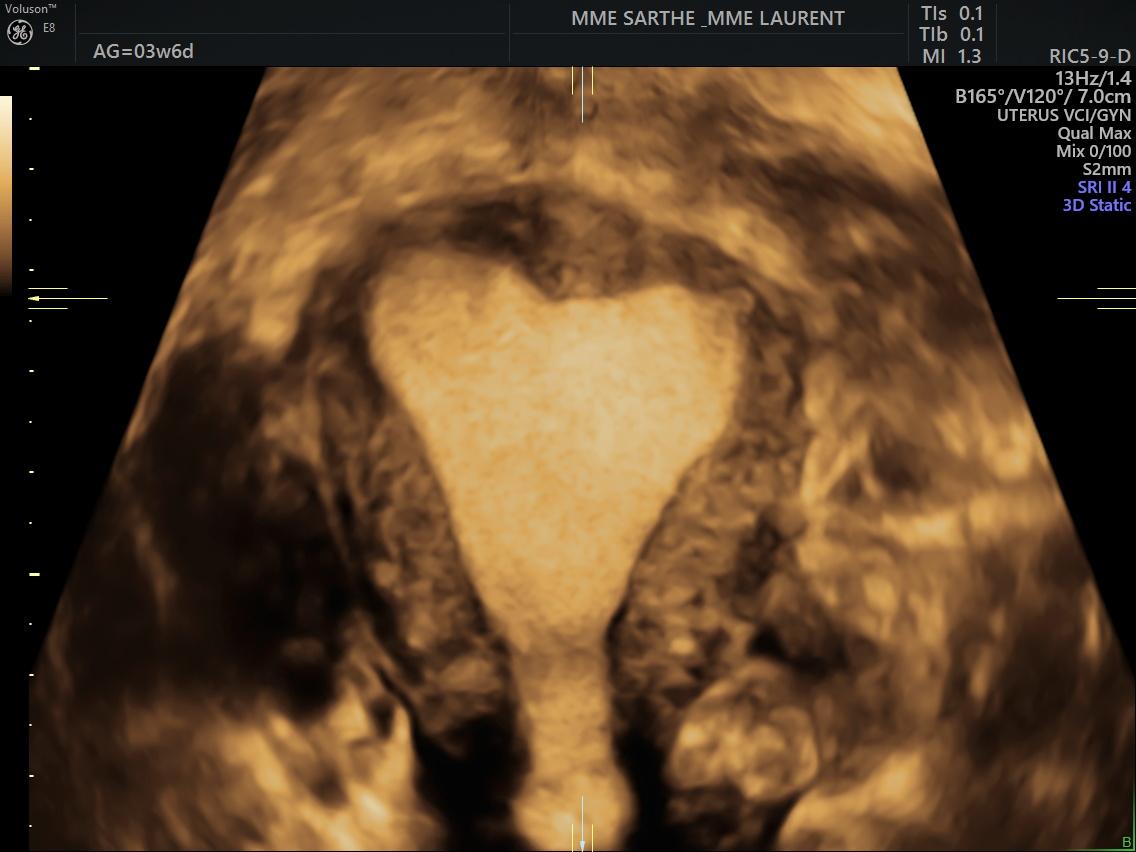

- l'échographie pelvienne

permet d'explorer les organes et tissus de la cavité pelvienne de la femme comme : la vessie, l’utérus et son col, les ovaires, les trompes de Fallope, la paroi séreuse, la paroi muqueuse, l’endomètre, le myomètre ainsi que la vascularité utérine, ovarienne et annexielle.

Elle est réalisée par voie endo-vaginale (sonde adaptée introduite dans le vagin). C'est un examen indolore.

Cet examen peut-être demandé en cas de kystes ovariens, de fibromes, de douleurs abdominales , de troubles du cycle et des règles, de vérification de dispositif intra-utérin...

Elle doit être réalisée vessie vide.